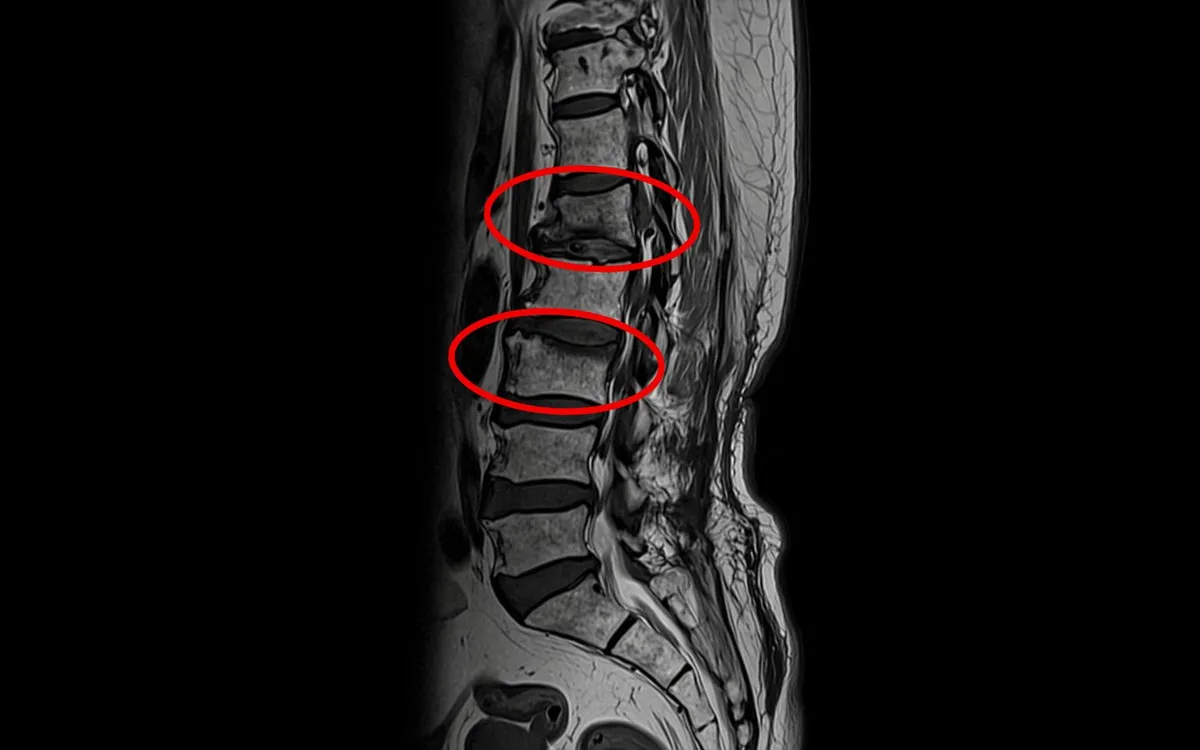

Quyết định đến Bệnh viện Đa khoa Hồng Ngọc thăm khám, kết quả chụp phim MRI cột sống và xét nghiệm cận lâm sàng ghi nhận bệnh nhân bị: xẹp cùng lúc 2 đốt sống do loãng xương nặng, hội chứng Cushing (do dùng corticoid), tăng huyết áp, rối loạn lipid máu, thiếu vitamin D.

Tình trạng xẹp đốt sống L1, L3 sau thời gian uống thuốc đông y không rõ nguồn gốc